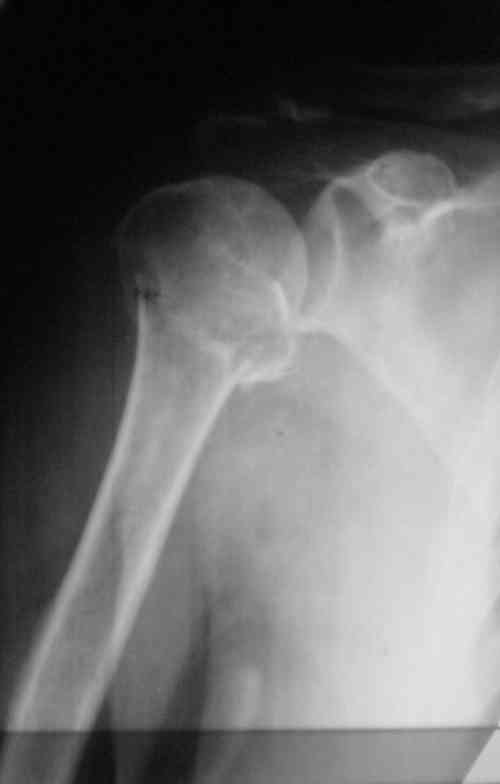

Судя по Р-граммам имеется оскольчатый перелом головки плеча. Во время открытой репозиции имеется большой риск "развалить" перелом, что значительно ухудшит кровоснабжения отломков. А так, на мой взгляд контакт м\у отломками достаточный, не смотря на наличие ротационного смещения головки думаю лучше продолжать консерватикное лечение. С уважением.

Судя по снимкам еще имеется перелом головки плеча, и чрезкостный отрыв вращательной манжеты. Для уточнения характера перелома не иешало бы сделать КТ. Если вести консервативно, то после сращения перелома будет ограничение движений в суставе не устраивающее больную. Я склоняюсь к оперативному лечению( накостный остеосинтез Т- Г образная пластина, лучше LCP для проксимальног плеча, обязательно подшить на место манжету).

В соответствии с работами Neer данный перелом можно классифицировать как однофрагментарный, так как нет диастаза более 1 см и углового смещения более 45 градусов - такие переломы лечатся консервативно. Рентген контроль каждые 10 дней- если смещение не увеличивается, то через 3-4 недели разработка движений в суставе

Уважаемый Сергей! Вы правильно написали критерии, но недооценили степень смещения в переломе хирургической шейки. Посмотрите ещё раз, это Two part fracture.

Снимки на 1-е сутки после репозиции и на 8- сутки после репозиции.

Пожалуйста

С ув. Sergey A. Melashenko, г. Запорожье